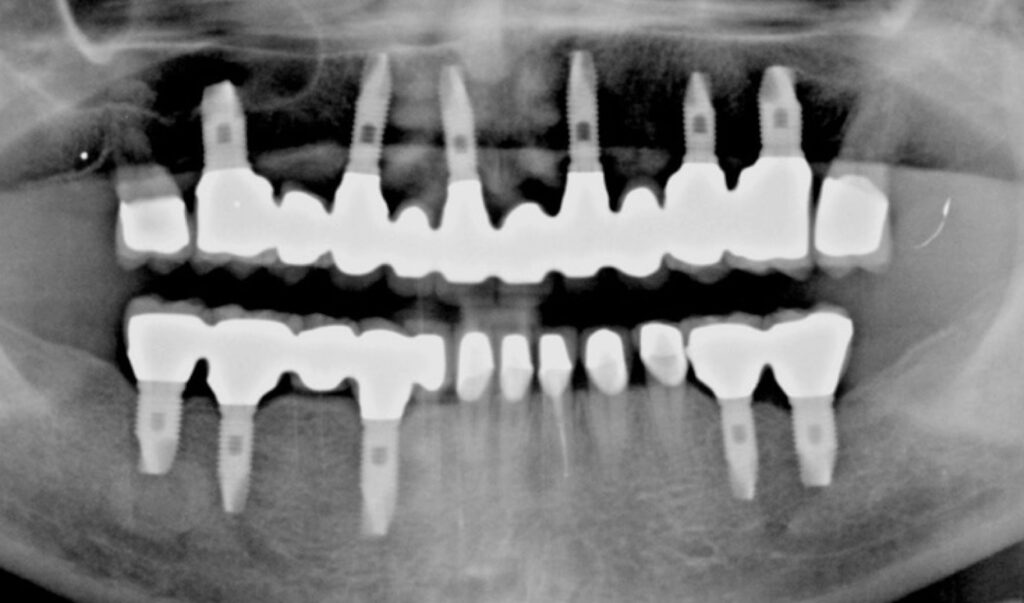

患者様のお悩み

食事ができない

治療法・使用素材

インプラントを用いた全顎的咬合治療

患者様の年代

40

治療開始年齢

49

治療にかかった期間

2年

性別

女性

治療後